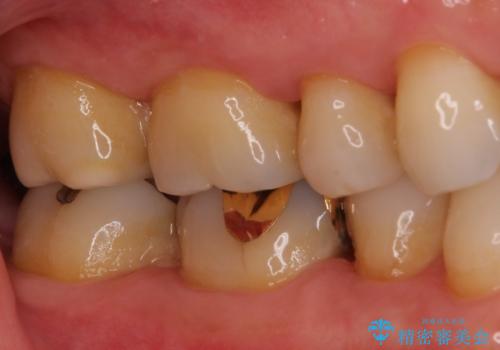

ゴールドインレーは銀歯のインレーやセラミックインレーと比べ、「技工操作の精度が高く、適合が著しく良い」というメリットがあります。特に上の奥歯は歯科医師の操作が行いにくいため、「適合の良さ」は再治療のリスクを防ぐ上でとても重要な要素となります。

上の奥歯は金属色が見えることもないため、審美的な問題は全くありません。

咬み心地はとても良好で、全く違和感がなく、患者様には大変満足していただきました。